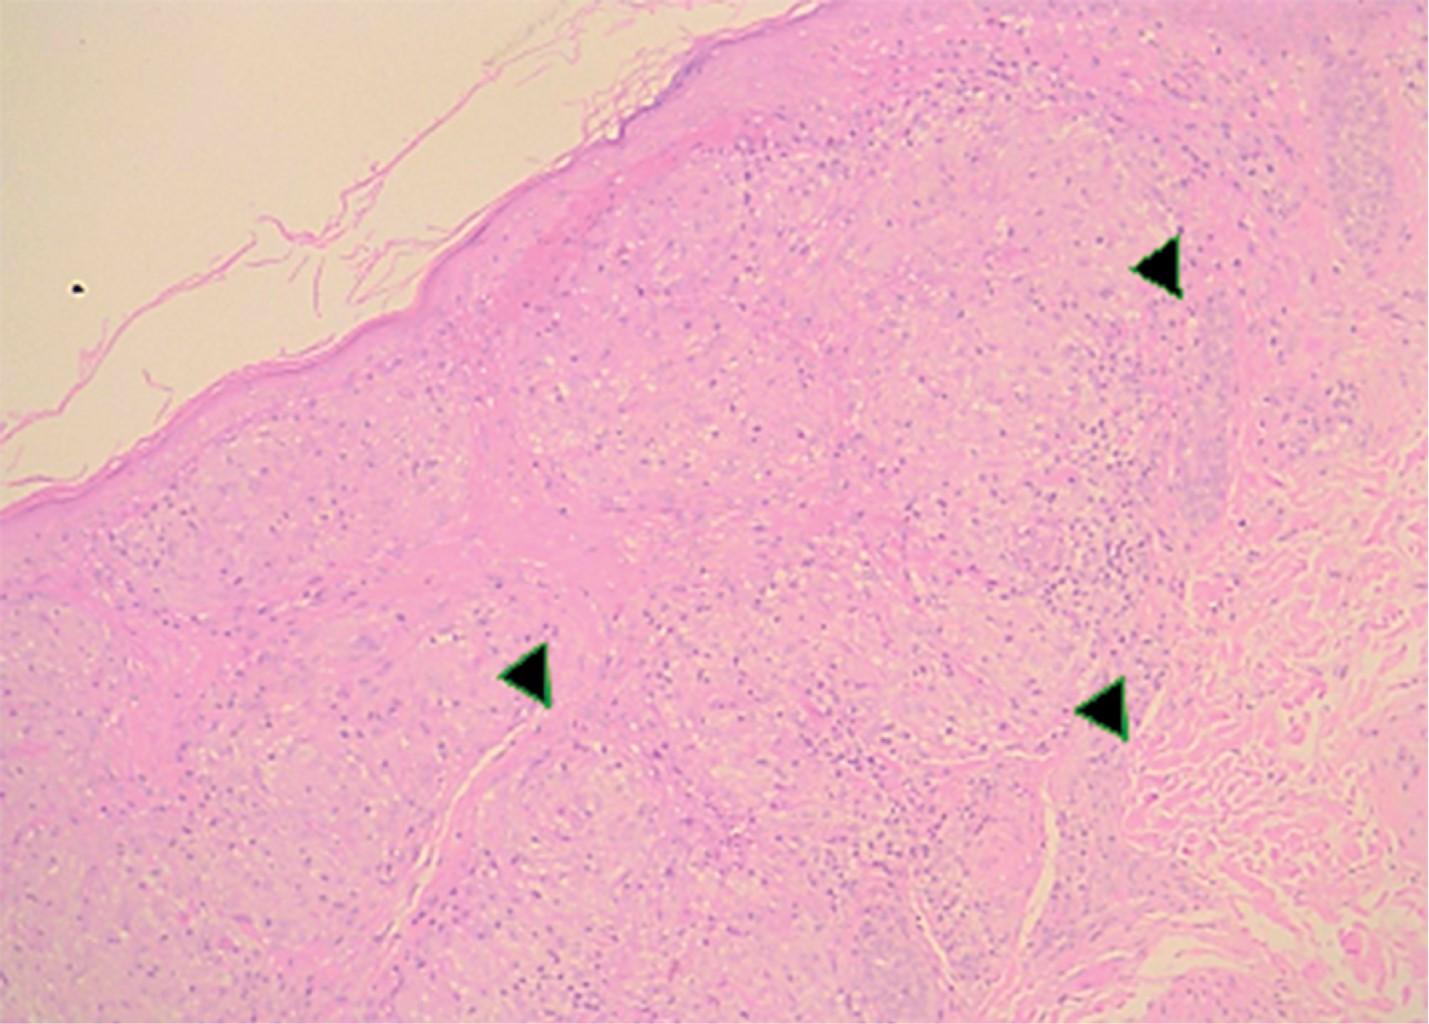

La biopsia renal mostró una nefritis granulomatosa tubulointersticial no caseificante con esclerosis global focal y datos anatómicos de arteriopatía hipertensiva (Figuras 4, 5 y 6).

La radiografía de tórax mostró ensanchamiento mediastinal y un patrón intersticial grueso a expensas de intersticio perilobulillar bilateral y difuso, casi simétrico con algunas imágenes nodulares también difusas (Figura 9). En la TACAR contrastada se corrobora el patrón intersticial perilobulillar con nódulos difusos con discreto predominio subpleural así como zonas de atelectasia bilateral subpleurales y en lóbulo medio (Figura 10). En la ventana mediastinal se demuestran crecimientos ganglionares paratraqueales de predominio derecho, en ventana aortopulmonar y axilar bilateral. A nivel abdominal lesiones nodulares hipodensas múltiples hepatoesplénicas sugestivas de granulomas (Figura 11). Se realizó biopsia de piel en cara, la cual mostró dermatitis granulomatosa epitelioide no caseificante, compatible con sarcoidosis (Figura 12).

El diagnóstico de sarcoidosis se confirma por la demostración de un granuloma no necrosante de células epitelioides típico en la biopsia,1,9,21,41,53 como ocurrió en ambos casos al demostrar dichos granulomas en la biopsia renal y de piel respectivamente.